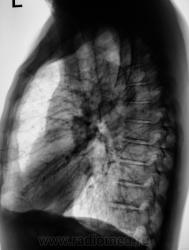

Позвал лаборант с флюорографа. Забрали в рентген-кабинет, сделали снимки в стандартных проекциях - прямая и правая боковая.

Боковая

Фрагмент с увеличением.